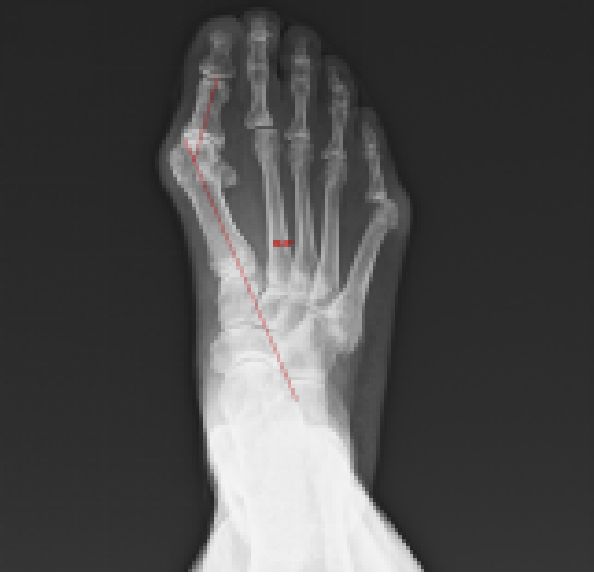

土踏まずと足背の痛みと変形 扁平足、有痛性外脛骨、リスフラン関節症

つま先の痛みと変形 外反母趾、強剛母趾、内反小趾、屈趾症、モートン病

の外科的治療:症例

保存療法では治療が見込めない患者様に対しては、人工足関節置換術、矯正骨切り術、遠位脛骨斜め骨切り術、関節固定術、血管柄付き腓骨移植、再建術などの外科的治療を提案をしております。

外科的治療:症例一覧